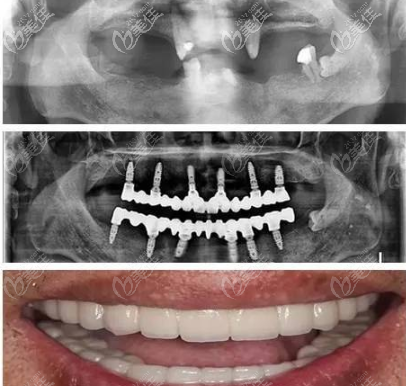

欣賞一個案例:

我爸爸做的是NobelSpeedy種植,已經(jīng)65歲了,他是上下頜的牙齒加起來就剩3顆了,之前戴的義齒,但是口腔一直出血,弄的很難受,我一氣之下,就給我爸爸做了種植。

老人真的不想花那么多錢,本來說選個便宜的種植體,但是我爸的條件本身就不好,怕選了便宜的還要出問題,就選的 NobelSpeedy的Shorty類型,我是趁著私立醫(yī)院搞活動的時候做的,花了15萬。